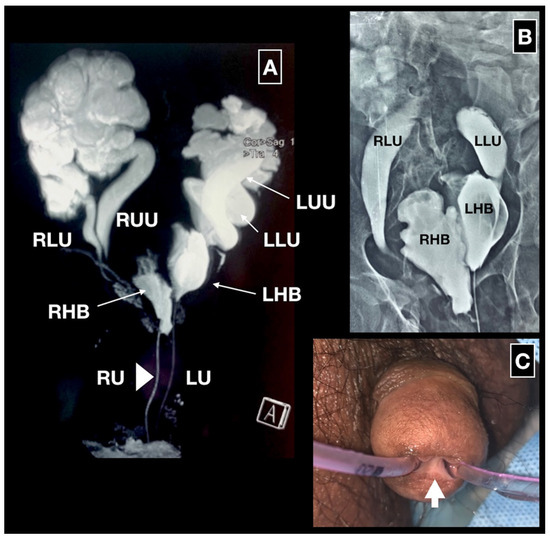

Figure 1 shows the first MRI image of complete urinary tract duplication demonstrating 2 renal pelves and 2 ureters on either side, 2 hemibladders (sagittal duplication) and 2 complete urethrae. Bilateral reflux into the lower moiety can be seen on dual urethrocystogram via both the urethrae. The glans showed 2 well-developed urethral meatuses with an intervening bridge of tissue consistent with Effman type III (complete) duplication [1].

Figure 1. MRI, dual urethrocystogram and clinical photograph of the glans. 1A. MRI shows 2 renal pelves and 2 ureters (RLU right lower moiety ureter, RUU right upper moiety ureter, LLU left lower moiety ureter, LUU left upper moiety ureter), the bladder split sagittally into 2 hemibladders (RHB right hemibladder, LHB left hemibladder) and complete duplication of the urethra (RU urethra draining the right hemibladder, LU urethra draining the left hemibladder). 1B. Retrograde urethrocystogram done via both the urethrae. The left hemibladder was placed somewhat cranial to the right one with reflux into bilateral lower ureters. 1C. Clinical photograph showing the 2 well-developed urethrae with an intervening bridge of tissue (arrow).